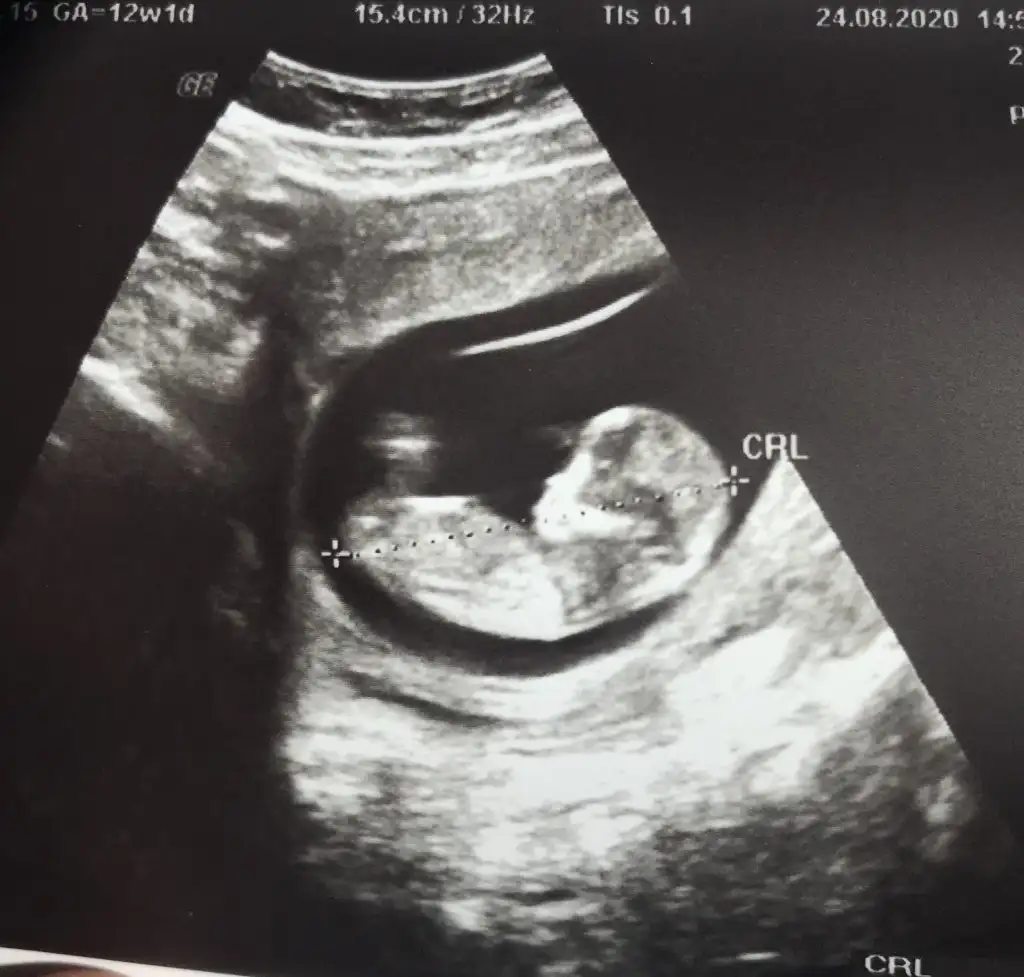

Erkek bebişMerhaba, 12. haftadan ultrason görüntülerimiz. Yorum yaparsanız çok sevinirim.Eki Görüntüle 2678844 Eki Görüntüle 2678845 Eki Görüntüle 2678846 Eki Görüntüle 2678844 Eki Görüntüle 2678845 Eki Görüntüle 2678846 Eki Görüntüle 2678844 Eki Görüntüle 2678845 Eki Görüntüle 2678846 Eki Görüntüle 2678846 Eki Görüntüle 2678844 Eki Görüntüle 2678845 Eki Görüntüle 2678846 Eki Görüntüle 2678844 Eki Görüntüle 2678845 Eki Görüntüle 2678846

Bana da öyle geldi bi de erkek olsa belli olurdu bu hafta dedi cogu kisi. Kız daha geç görünüyormuş bakalım ne cikacak iki hafta sonra yazarımKız gibi sanki